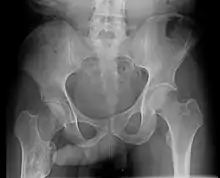

The John Thomas sign,[1] also known as the Throckmorton sign,[2] is a slang or joke term used in the field of radiology. It refers to the position of a penis as it relates to pathology on an X-ray of a pelvis. When the penis (visible on the X-ray as a shadow) points towards the same side as a unilateral medical condition such as a broken bone, this is considered a "positive John Thomas sign", and if the shadow points to the other side, it is a "negative John Thomas sign."[3]

Studies have shown that the "sign" is no better than chance at identifying the location of a hip fracture.[4][5] In those cases where the John Thomas sign is positive, it has been proposed that a person with a displaced hip fracture may try to lie on the injured side to immobilize the fracture and reduce pain; the penis then inclines toward the downward (injured) side.[6]

Andy Murray, British professional tennis player, released a picture of his pelvic X-ray following his hip resurfacing surgery on January 29, 2019[7] clearly demonstrating an example of a negative John Thomas or Throckmorton sign where his penis pointed away from the site of injury. The release of the X-ray image with visible genitalia was discussed by Piers Morgan on Good Morning Britain prompting Murray, who was watching at the time, to message the show, stating, "Please can you stop discussing my genitals on national TV, I was heavily medicated at the time of posting."[8]